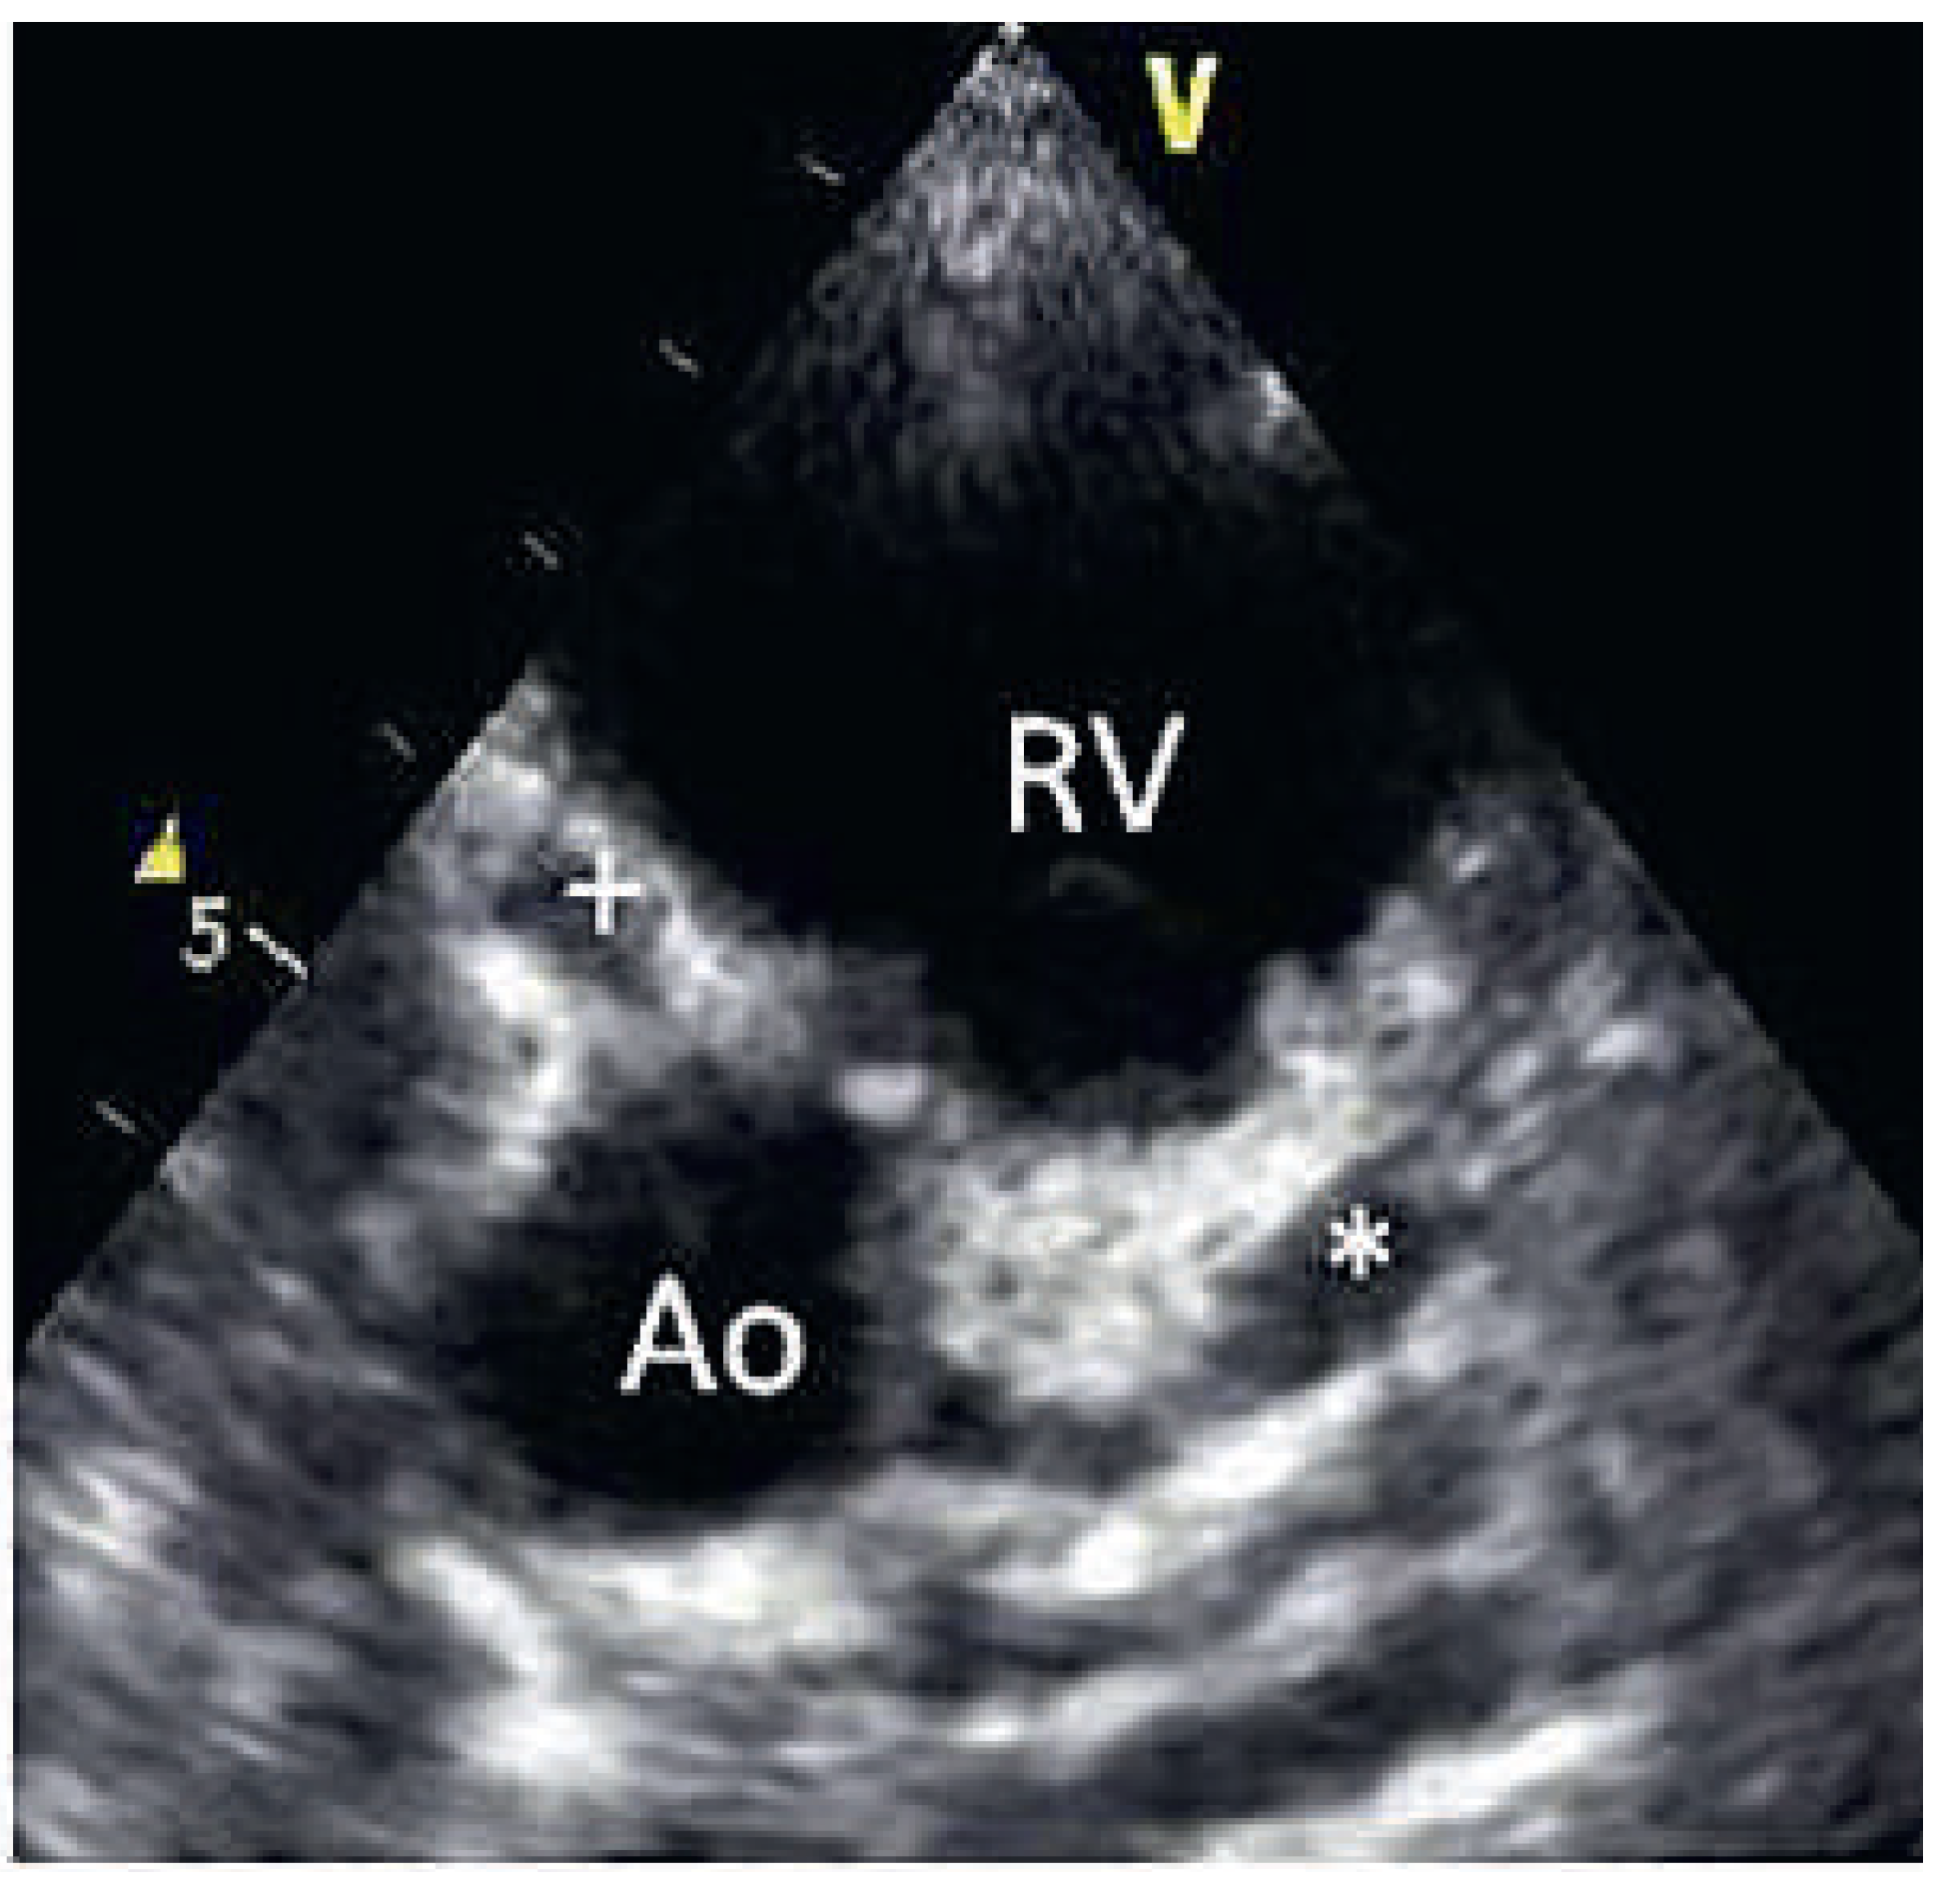

On the tenth day, we performed transthoracic echocardiography (Figure 1 and Figure 2), which revealed normal biventricular size and function, without hypokinesia. There was no pericardial effusion, no valvular disease, but a proximal enlargement of the left anterior descending coronary artery (LAD) was visualised. On the same day, because all these elements suggested Kawasaki disease (KD), treatment with intravenous polyvalent immunoglobulin (IVIG 2 g/kg as a single infusion: Privigen 70 g) and high-dose aspirin (80 to 100 mg/kg/d: 750 mg four times a day for eight days) was started, with rapid resolution of symptoms and apyrexia within 24 hours. Cardiac computed tomography (CT; Figure 3) showed three-vessel aneurysmal coronary artery disease (CAD) including a giant aneurysm of the proximal LAD (9 mm), an aneurysm of the circumflex artery (6 mm) and two aneurysms of the right coronary artery (4 and 5 mm). There was no vascular involvement in the cerebral and abdominal magnetic resonance imaging (MRI).

Figure 1.

2D echocardiography (* = left anterior descending artery aneurysm).